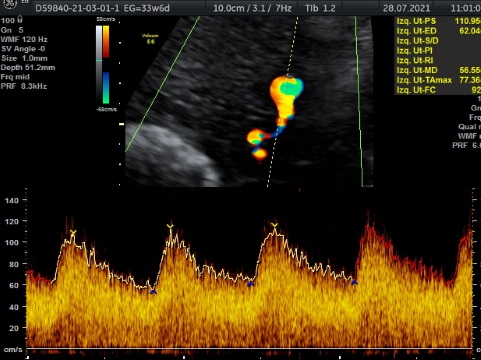

En cualquier semana de embarazo. Es un estudio que nos habla de la oxigenación que esta teniendo tu bebé a través de diferentes flujos sanguíneos ( cordón umbilical, cerebero, arterias uterinas, flujos del corazón. Es un estudio que se realiza para verificar Bienestar Fetal. Tiene una duración de 1 hora y al finalizar el estudio , se realiza 3D, 4D, 5D. Costo $1600